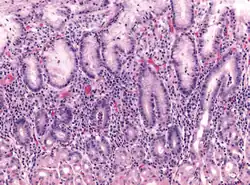

Micrograph showing gastritis. H&E stain.

Gastritis is the inflammation of the lining of the stomach.[1] It may occur as a short episode or may be of a long duration.[1] There may be no symptoms but, when symptoms are present, the most common is upper abdominal pain (see dyspepsia).[1] Other possible symptoms include nausea and vomiting, bloating, loss of appetite and heartburn.[1][2] Complications may include stomach bleeding, stomach ulcers, and stomach tumors.[1] When due to autoimmune problems, low red blood cells due to not enough vitamin B12 may occur, a condition known as pernicious anemia.[3]